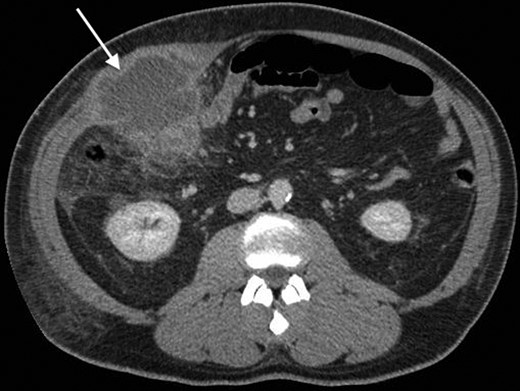

His past surgical history included conservatively managed renal calculi and left inguinoscrotal herniorrhaphy. Right hypochondrial palpation identifying a tender, well-defined, hard, smooth edged, non-pulsatile, non-fluctuant mass (10 × 9 cm). Observations were within normal limits and systemic examinations unremarkable. Haematological results showed the following: albumin 27, WCC 15.7, neutrophils 11.0, CRP 341, amylase 20. Urinalysis, chest and abdominal radiographs (AXR) were normal. Initial resuscitative management was commenced and a contrast enhanced computed tomography (CT) performed. This demonstrated an anterior abdominal wall collection (7 cm) arising from an RUQ appendiceal abscess secondary to acute appendicitis (Figs 1 and 2). Consequent ultrasound (US) guided drainage and pigtail catheter insertion removed 50 ml of frank pus, which isolated pathogens sensitive to penicillin and erythromycin. Following 3 days of intravenous piperacillin and tazobactam (Tazocin®) he was discharged with oral erythromycin. An out-patient barium follow-through and colonoscopy were unremarkable.

A coronal CT with contrast showing the tail of the appendix communicating with the appendiceal abscess.